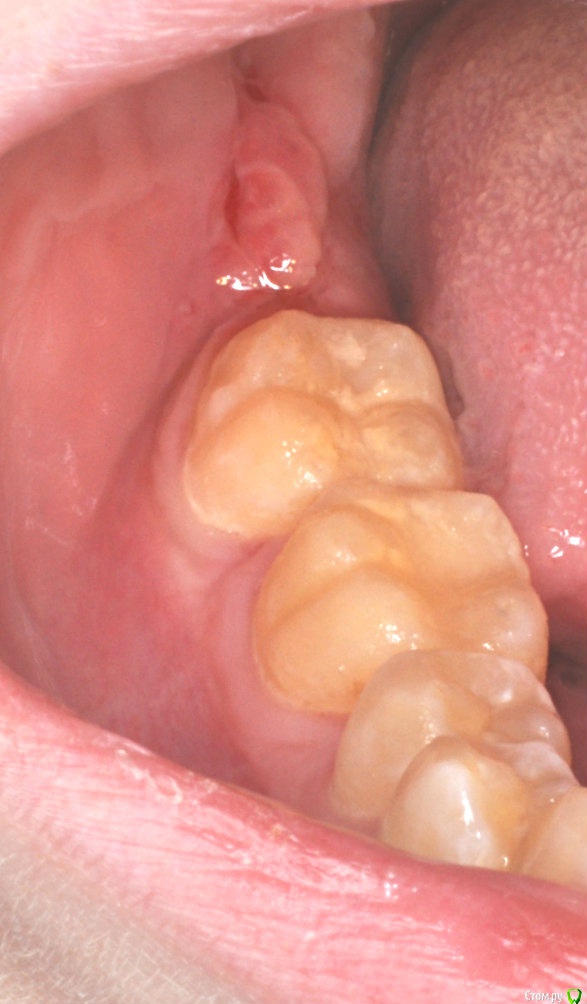

колесников Опубликовано 16 апреля, 2017 Автор Поделиться Опубликовано 16 апреля, 2017 Иногда кажется ,что лоскут выделить язычно не возможно и наглухо ушить не удасться,особенно в случаях когда 8ка полностью прорезалась. Это только так кажется. Ссылка на комментарий

Irouil Опубликовано 16 апреля, 2017 Поделиться Опубликовано 16 апреля, 2017 Графт был? Ссылка на комментарий

колесников Опубликовано 17 апреля, 2017 Автор Поделиться Опубликовано 17 апреля, 2017 К сожалению нет. Ссылка на комментарий

Irouil Опубликовано 17 апреля, 2017 Поделиться Опубликовано 17 апреля, 2017 Я никак в толк взять не могу - это расщепленный и опрокинутый? Или развернутый? Кажется будто первый вариант, но как его оттуда расщеплять ума не приложу. А если второй, то он все равно ведь только щель прикрывает, верно? (Справедливости ради только с ней и бывают проблемы обычно) Ссылка на комментарий

колесников Опубликовано 17 апреля, 2017 Автор Поделиться Опубликовано 17 апреля, 2017 (изменено) В данном случае развёрнутый. Опрокинутый когда 8ка не прорезалась,самый простой вариант. Да,в щели вижу всю проблему вторичного инфицирования,для прикрытия вероятного расхождения краев раны за 7кой,делаю второй лоскут. Изменено 17 апреля, 2017 пользователем колесников Ссылка на комментарий